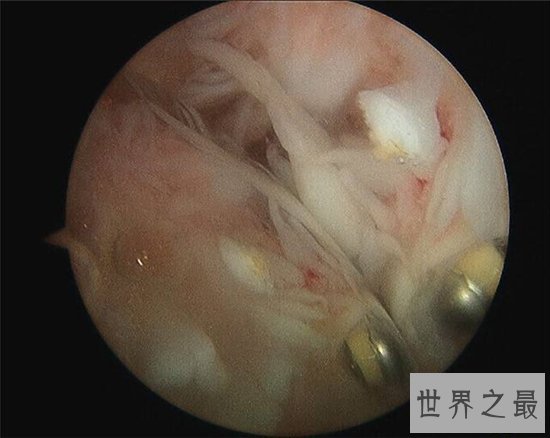

6、关节镜

关节镜是目前大范围用于骨骼检查的医疗手段,可以以关节镜深入人体内部来探查是否病变,许多骨科炎症例如关节炎都是通过这种检查发现的。关节镜是我们需要定期进行的必要检查,也是进行手术时常用的辅助器械。